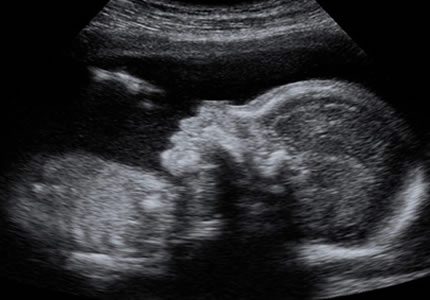

Early Pregnancy Scans (6 – 16 Weeks)

- This essential early assessment is designed to provide clarity during the first few weeks. We confirm that the pregnancy is developing in the correct position (intrauterine) and visualise the fetal heartbeat. It is a vital milestone for those who want immediate reassurance or have experienced complications in the past.

- £79

- This scan provides a precise Estimated Date of Delivery (EDD) by measuring your baby from head to bottom (Crown-Rump Length). It is the most accurate way to date your pregnancy, making it ideal for those with irregular cycles or for anyone who missed their initial NHS screening.